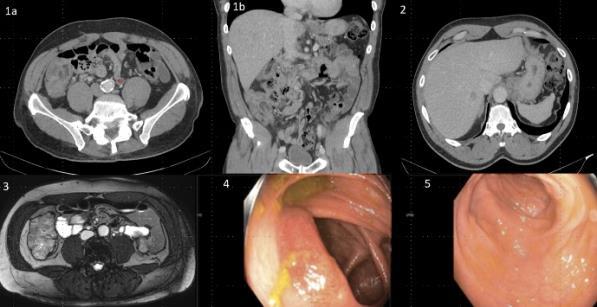

CASE PRESENTATION: A 67-year-old male with a history of partial liver resection, peptic ulcer disease, and Helicobacter pylori gastritis s/p quadruple therapy presented with acute on chronic abdominal pain despite being on a proton pump inhibitor (PPI). He had abdominal pain for the past 5 years associated with nausea, vomiting, diarrhea, and a 50-pound unintentional weight loss. An esophagogastroduodenoscopy (EGD) six months ago demonstrated peptic ulcer disease and Helicobacter pylori which was successfully eradicated.

He underwent a CT-abdomen/pelvis with intravenous contrast in the emergency department which revealed an enhancing 3.4 cm mass in the head of the pancreas with retroperitoneal lymphadenopathy. MRI of the abdomen confirmed the presence of a 3.2 cm enhancing pancreatic head mass with direct extension into the second portion of the duodenum and multiple enlarged retroperitoneal lymph nodes. EGD was remarkable for edema and granularity in the first portion of the duodenum. Endoscopic ultrasound (EUS) was notable for a hypoechoic and heterogeneous irregular mass in the pancreatic head measuring 25 mm by 23 mm in maximal crosssectional diameter with invasion into the serosa and muscularis mucosa of the duodenum. Fine needle aspiration of the pancreatic mass for cytology revealed a well-differentiated pancreatic neuroendocrine tumor (Ki-67 index <1%). Gastrin levels were ordered. He presented again to the hospital 3 weeks later with worsening epigastric abdominal pain and nausea despite adhering to PPI therapy. CT-abdomen revealed new proximal duodenal ulcerations. Gastrin level from the prior admission was noted to be 1988 pg/mL. He subsequently underwent a Whipple's procedure with no complications and was discharged home with a planned EGD surveillance in 6 months.

CONCLUSION: Establishing a diagnosis of ZE can be difficult due to the lack of consistent diagnostic criteria, the widespread use of PPIs that masks mask the symptoms and limited access to gastric pH testing. In our case, the diagnosis was based on a fasting serum gastrin level, FNA results, and imaging findings. Owing to its variable clinical presentation, high mortality, and challenging primary lesion identification, clinicians should consider ZE in the differential diagnosis of patients who are symptomatic despite taking PPI, having Helicobacter pylori successfully eradicated or having multiple duodenal and gastric ulcers that fail to respond to therapy.

Figure 1: CT Abdomen and Pelvis with contrast showing a suspicious mass in the second portion of the duodenum/pancreatic head.